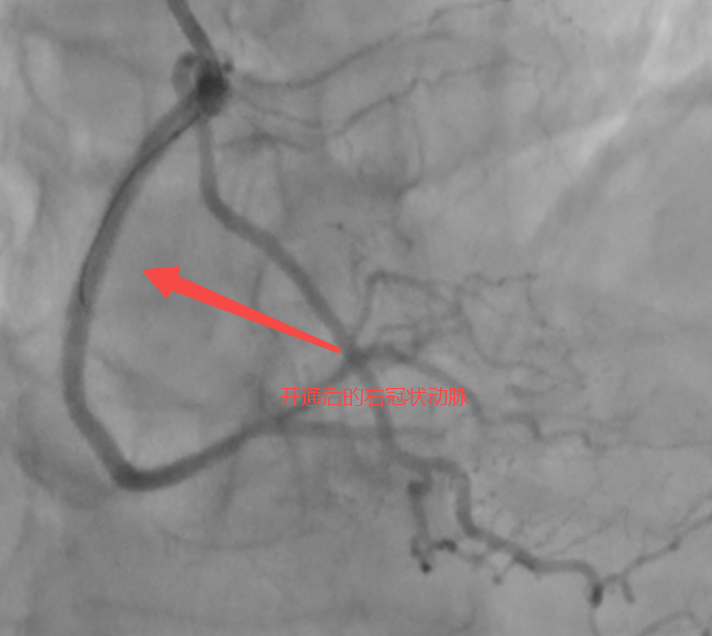

术中,马志强主任团队启用三维冠脉造影精准定位侧支路径,以头发丝般纤细的导丝,在侧支血管中实现“毫米级”推进,成功建立逆向通路。随后通过多项正向、逆向技术成功打通血管并植入药物支架,恢复右冠脉血流。术后患者胸闷症状缓解,次日即可下床活动,目前已顺利出院。

马志强主任介绍,“逆向介入手术”主要有三大难点:第一,侧支血管极其纤细,需在直径不足0.5mm的侧支血管中精准操作,稍有不慎就会导致血管破裂;第二,逆向操作风险极高,导丝逆向通过后需确保正向血流恢复,技术难度远超常规手术;第三,重建血管通路,成功开通后,需要精准植入可释放药物的支架,撑开血管,恢复有效血流。